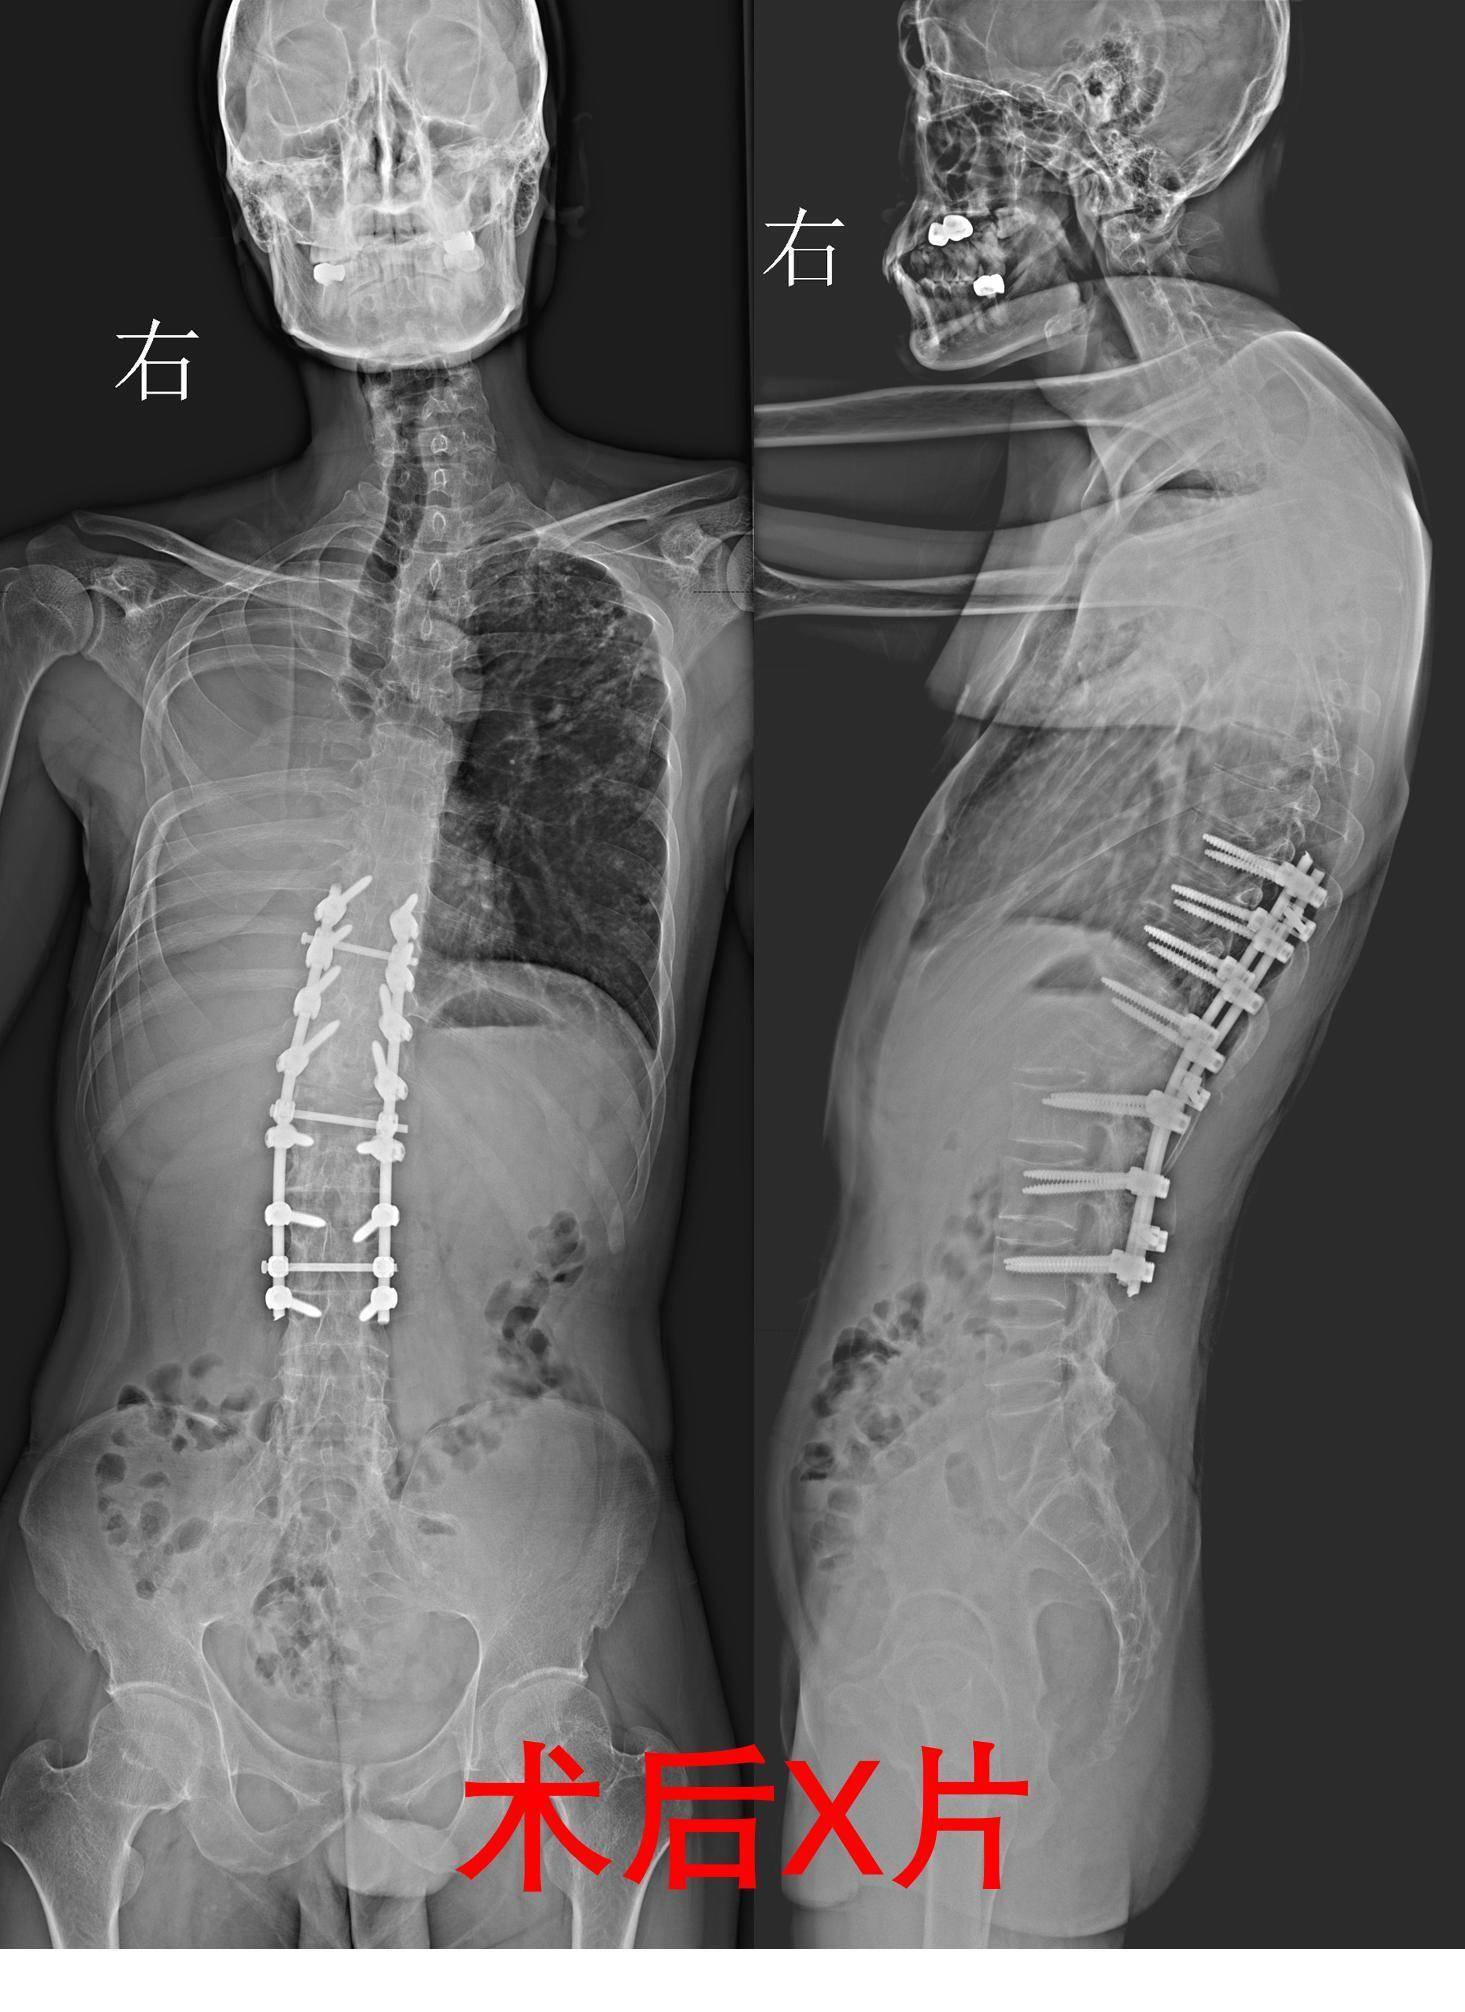

为给唐先生制定最安全的方案,梁益建教授和楚磊教授团队开展周密讨论,确定“曲线救国”的手术策略:通过脊柱后路截骨矫形植骨融合椎弓根螺钉内固定术,将截骨位置确定在腰1椎体,避开对胸廓的干扰,最大限度保护仅存的肺功能。

手术当天,梁益建教授带领楚磊教授、赵登副主任医师、张钟主治医师,在显微镜下细心松解粘连的脊髓和神经,精准截除部分椎体及周围骨组织,将弯曲的脊柱重新排列……为追求完美矫形效果,61岁的梁益建教授多次跪地,查看患者脊柱矫形是否达到预期效果。“跪地只为看得更清晰,患者很年轻,尽量一次手术给他解决问题。”

手术历时5小时,十分顺利。术后,经过精心医治,目前,唐先生已能下地活动,外观改善明显。“主动要求手术,是我这辈子最正确的决定。”他感慨道,提醒人们一旦腰骶部疼痛,尽早就医。若确诊强直性脊柱炎,尽早干预。